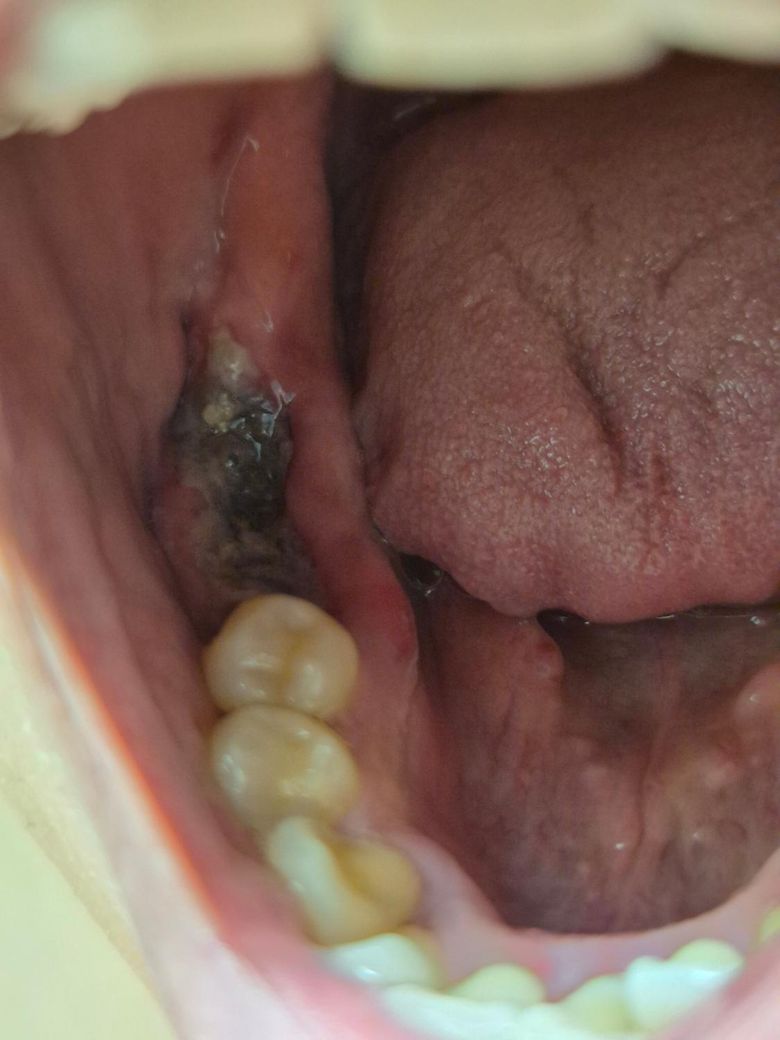

발치 후 치료과정 2일차 소견문의 드립니다.

#47, 46 ? 으로 기억하는데

어금니와 그 앞에 치아 두개 한번에 발치했습니다.

발치는 화요일에 했으나, 수요일까지 출혈이 있었습니다.

수요일오후부터 지혈이 되었으니 작성일 기준 금요일 오후,

대략 48시간 지난 후 상태입니다.

현재 정상적으로 아무는중인지 문의 드립니다.

• 1번 째 사진

사진상으로 보면 지혈도 잘된거 같고 잇몸도 잘 아물고 잇는거 같으니 크게 걱정하지 않으셔도 될것같습니다.

아직 발치 후 이틀밖에 안된 상태라 치유 상태가 어떠하다고 말하기는 애매합니다. 약 복용으로 통증 잡힌다면 괜찮은겁니다. 진통제는 부족하면 집에있는 상비약(타이레놀 계열)드시면 됩니다.